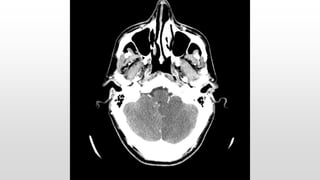

This document discusses various cases of collapse and syncope. It defines collapse as transient loss of consciousness with loss of postural tone and full recovery. Syncope is defined as loss of postural tone with or without loss of consciousness and full recovery. It then discusses the multiple potential causes of collapse and syncope including toxicological, cardiac conduction abnormalities, structural cardiac issues, autonomic dysfunction and more. It then goes through 9 case examples, discussing important questions to ask, potential tests and interventions for each case.